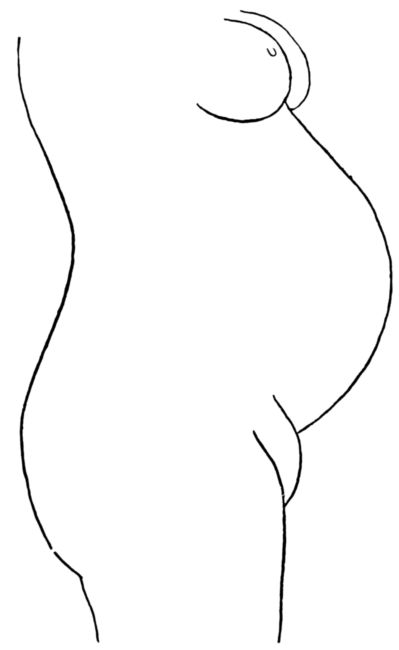

| 34. | Front view of home-made abdominal binder | 123 |

| 35. | Side view of same | 123 |

| 36. | Back view of same | 123 |

| 37. | Abdominal binder used in above | 124 |

| 38. | Front view of home-made stocking supporters | 124 |

| 39. | Back view of same | 124 |